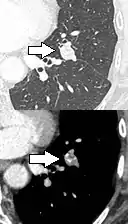

- Bubble-like lucencies in the nodule indicate cancer:[9]

.png.webp)

- Vascular convergence is where vessels converge to a nodule without adjoining or contacting the edge of the nodule, and is mainly seen in peripheral subsolid lung cancers.[9] It reflects angiogenesis.[9]